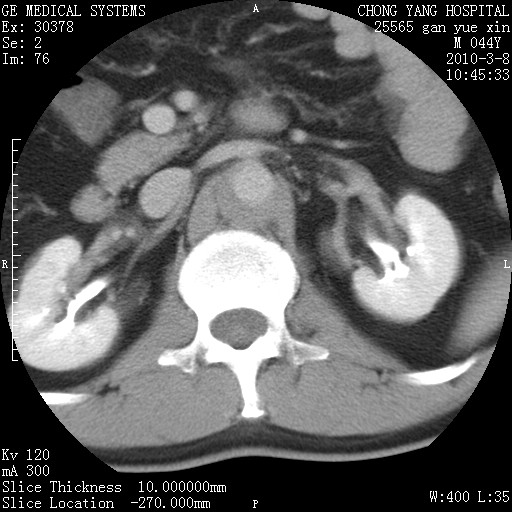

标题: CT24940:主动脉增强,典型病例。 [打印本页]

标题: CT24940:主动脉增强,典型病例。

夹层动脉瘤。

动脉夹层

夹层动脉瘤,典型

主动脉夹层。

动脉夹层的分型:

⒈debakey分型:根据主动脉夹层累及部位,分为三型:ⅰ型:原发破口位于升主动脉或主动脉弓部,夹层累及升主动脉、主动脉弓部、胸主动脉、腹主动脉大部或全部,少数可累及髂动脉。ⅱ型:原发破口位于升主动脉,夹层累及升主动脉,少数可累及部分主动脉弓。ⅲ型:原发破口位于左锁骨下动脉开口远端,根据夹层累及范围又分为ⅲa,ⅲb。ⅲa型:夹层累及胸主动脉。ⅲb型:夹层累及升主动脉、腹主动脉大部或全部。少数可累及髂动脉。

⒉stanford分型:a型:夹层累及升主动脉,无论远端范围如何。b型:夹层累及左锁骨下动脉开口以远的降主动脉。

夹层动脉瘤,少量胸水

夹层动脉瘤;左侧少量胸腔积液。

典型主动脉夹层。